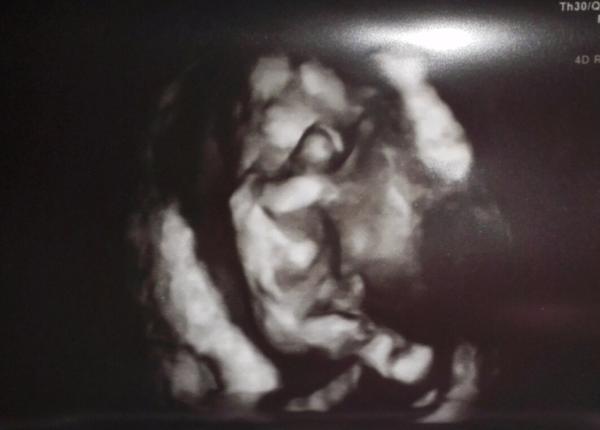

UFO z vesmíru

tys tak jednou taky vypadal(a),a,možná to trvá i dál😀 😀 😀

Teď vidím, že se mi to seřadilo naopak, takže první fotka je 12. týden a pak dvě z 13. týdne.